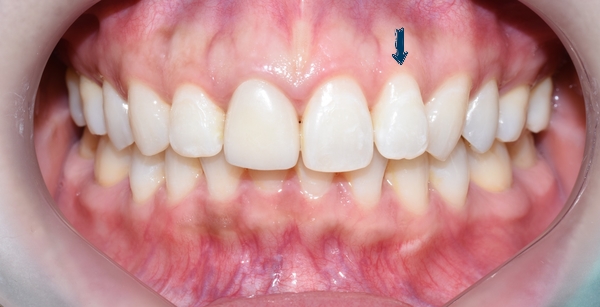

서울 시청역 연세예감치과 [사진공개 동의한 환자분 사진입니다.]

이번 소개해 드릴 분은 몇 년 전 다른 치과에서 교정을 하셨는데

다시 앞니가 튀어나와보인다는 것을 해결하기 위해 오신 환자분입니다.

많이 튀어나오진 않았지만, 유독 이런 이가 사진을 찍을 때 도드라지게 보이죠.

사진에서 한 치아가 옆 치아들과 비교해 유독 튀어나온 것 같은 느낌? 있으시죠?